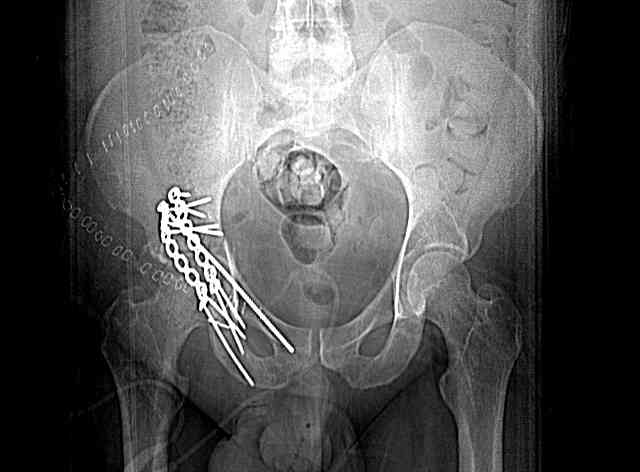

good morning,

the case that I found is a 20yo male, MCC. his AP pelvis shows an interesting position of his bladder. it is pushed aside by a hematoma from SGA injury. we did a limited lateral window approach for the anterior column first, pt bumped up/supine. then closed and repositioned for KL. I could not find intra-op photos of cases when we did only a small incision for the AC screw (but they do exist!!). the lateral window is available for reduction assessment if a KL approach is being used. in the lateral position this window is available. the prone position definitely takes pressure off of the post column and facilitates reduction. in the lateral position a schantz pin in the ischial tub +/- bone hook in sciatic notch helps with PC reduction. the lateral position also gives better airway access for anesthesia. airway problems are rare, but prone position seems to be a bit more of a challenge to exchange the tube, or reintubate altogether. just something further to debate!